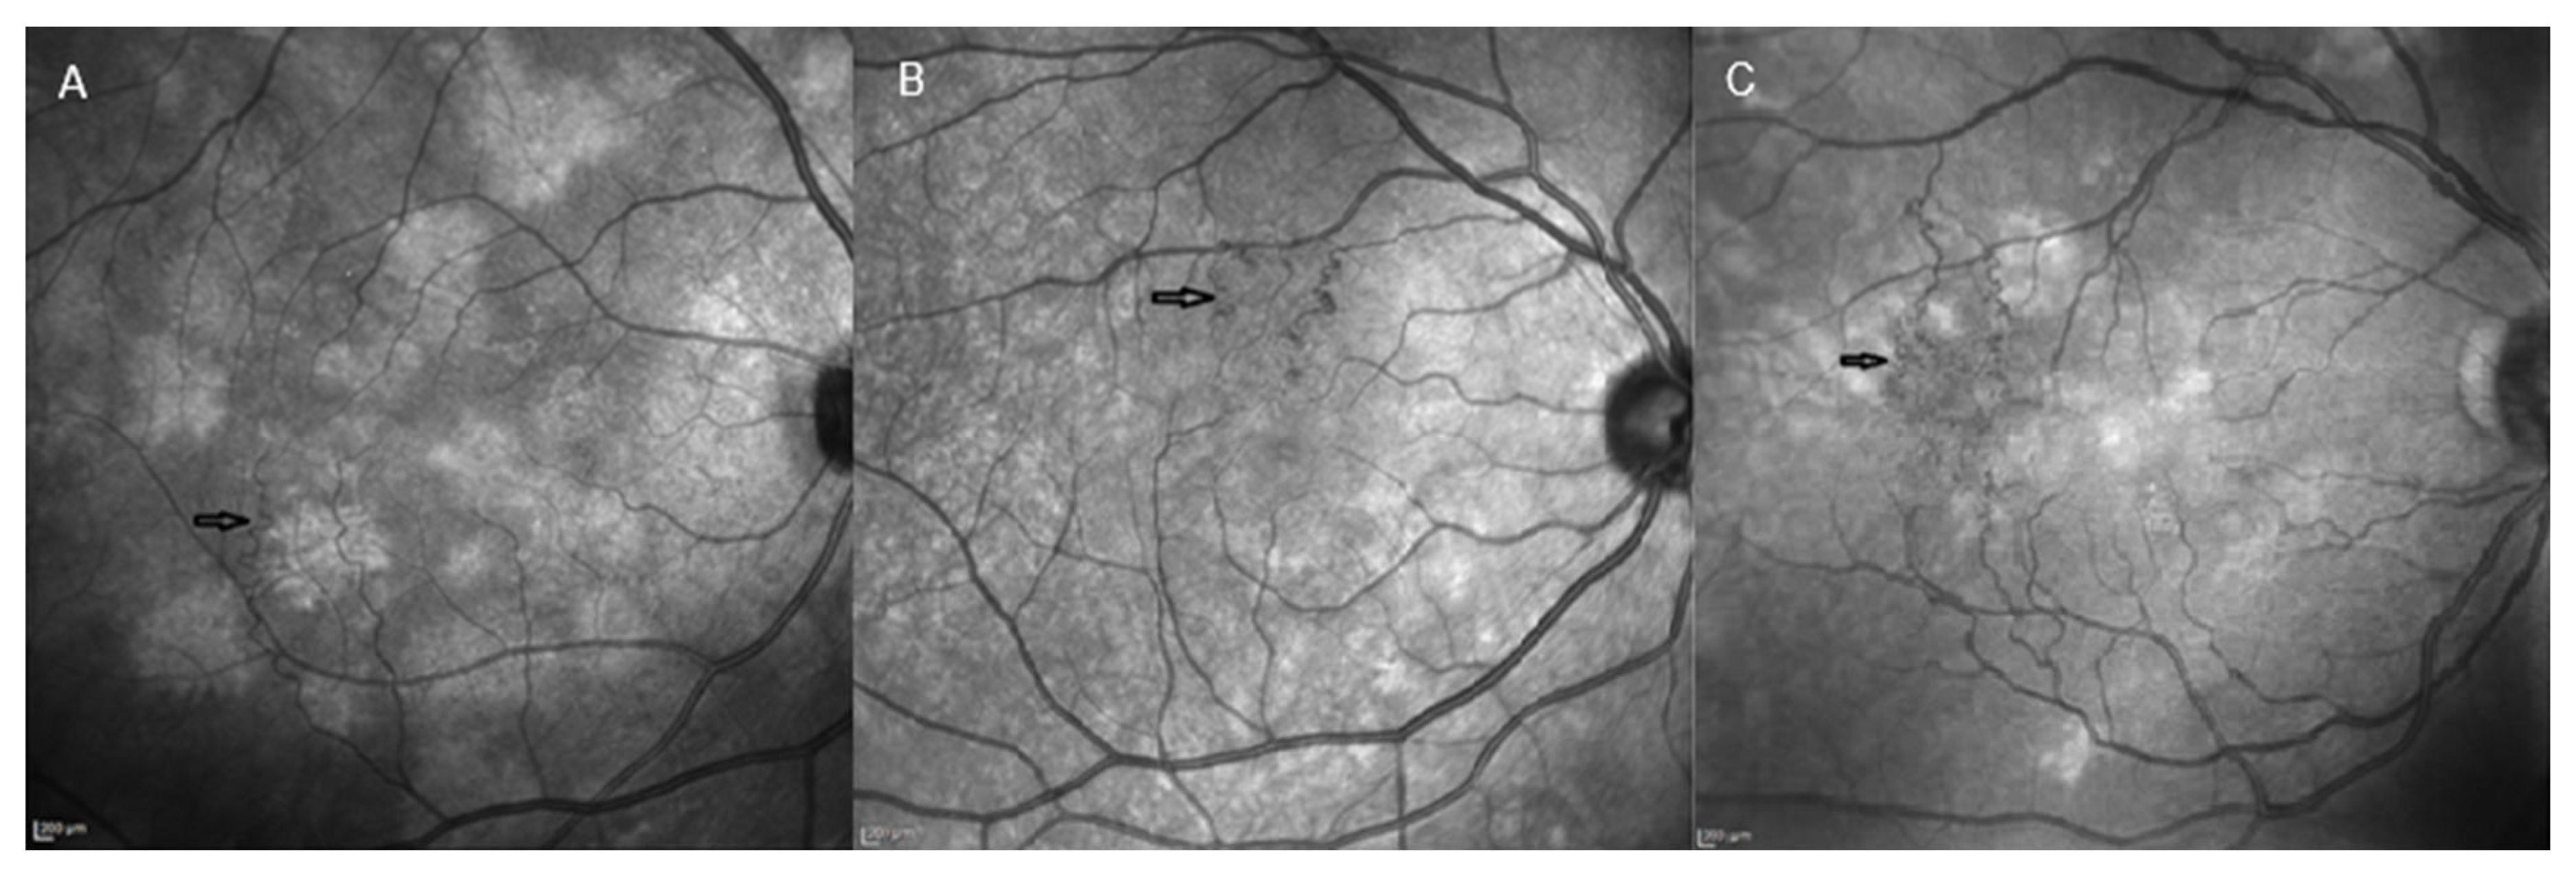

- Parrozzani, R.; Frizziero, L.; Trainiti, S.; Calciati, A.; Londei, D.; Miglionico, G.; Trevisson, E.; Midena, G.; Pilotto, E.; Midena, E. Retinal vascular abnormalities related to neurofibromatosis type 1: Natural History and Classification by Optical Coherence Tomography Angiography in 473 Patients. Retina 2021, 41, 979–986. [Google Scholar] [CrossRef] [PubMed]

- Parrozzani, R.; Pilotto, E.; Clementi, M.; Frizziero, L.; Leonardi, F.; Convento, E.; Miglionico, G.; Pulze, S.; Perrini, P.; Trevisson, E.; et al. Retinal vascular abnormalities in a large cohort of patients affected by neurofibromatosis type: 1 a study using optical coherence tomography angiography. Retina 2018, 38, 585–593. [Google Scholar] [CrossRef]

- Moramarco, A.; Miraglia, E.; Mallone, F.; Roberti, V.; Iacovino, C.; Bruscolini, A.; Giustolisi, R.; Giustini, S. Retinal microvascular abnormalities in neurofibromatosis type 1. Br. J. Ophthalmol. 2019, 103, 1590–1594. [Google Scholar] [CrossRef]

- Touzé, R.; Abitbol, M.M.; Bremond-Gignac, D.; Robert, M.P. Retinal vascular abnormalities in children with neurofibromatosis type 1. Retina 2021, 41, 2589–2595. [Google Scholar] [CrossRef]